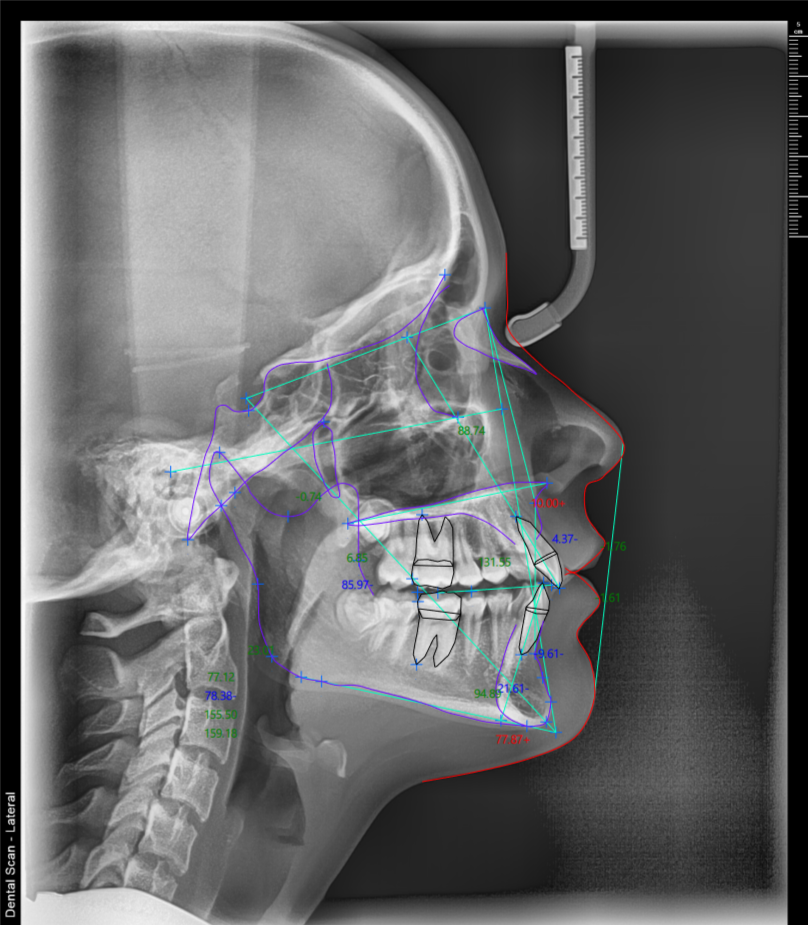

Telerendgen uz pomoć veštačke inteligencije – 15 analiza za 5 minuta

U našem Dental Scan centru, svaki telerendgen snimak se digitalno obrađuje pomoću softvera zasnovanog na veštačkoj inteligenciji.

AI tehnologija automatski prepoznaje cefalometrijske tačke na telerendgen snimku, čime se eliminiše manuelno obeležavanje i smanjuje mogućnost greške u ortodontskoj analizi.

Na osnovu jednog telerendgen snimka, moguće je digitalno izraditi do 15 ortodontskih analiza u roku od svega nekoliko minuta, uključujući:

Zahvaljujući digitalnoj obradi, telerendgen snimak postaje pouzdana osnova za planiranje ortodontske terapije i praćenje rezultata tokom vremena.